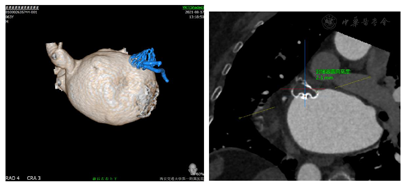

为缩短手术时间及减少手术步骤,术前同时采用CT评估了最佳展开体位及理想的穿刺部位。采用CT模拟后发现在RAO30 CAU25时为最佳工作体位(图3)。由于左心耳常规穿刺部位为靠下靠后,但通过CT模拟后发现当靠下靠前穿刺房间隔可以保持更好的轴向,利于术中的操作(图4)。

穿刺成功先行房颤射频消融治疗,消融完成后更换左心耳封堵鞘,以猪尾导管保护于RAO30° CAU25°造影,左心耳形态充分暴露,可以观察到心耳属于反鸡翅形状。内部梳状肌较发达,深度较浅。DSA测量开口18mm,深度19mm,与CT测量结果类似,考虑选择24mm watchman封堵器,首选X3轴向进行封堵。术中在猪尾导管的保护下,逆时针旋转输送鞘,尽量将输送鞘送入上叶。稳定输送系统,体外预借2mm深度,送入封堵伞,逆时针旋转稳定输送鞘,术中缓慢释放封堵伞,释放后稳定5分钟后造影提示封堵完全,上缘轻度露肩,行TEE检查未见残余分流,压缩比测量12.5%~21%(图7,图8),经牵拉测试稳定,符合PASS原则,决定释放封堵器,释放后再次造影提示封堵完全(图9)。术后患者顺利清醒,术后6小时检测无心包积液,加用达比加群110mg 2次/天;术后第五天出院。